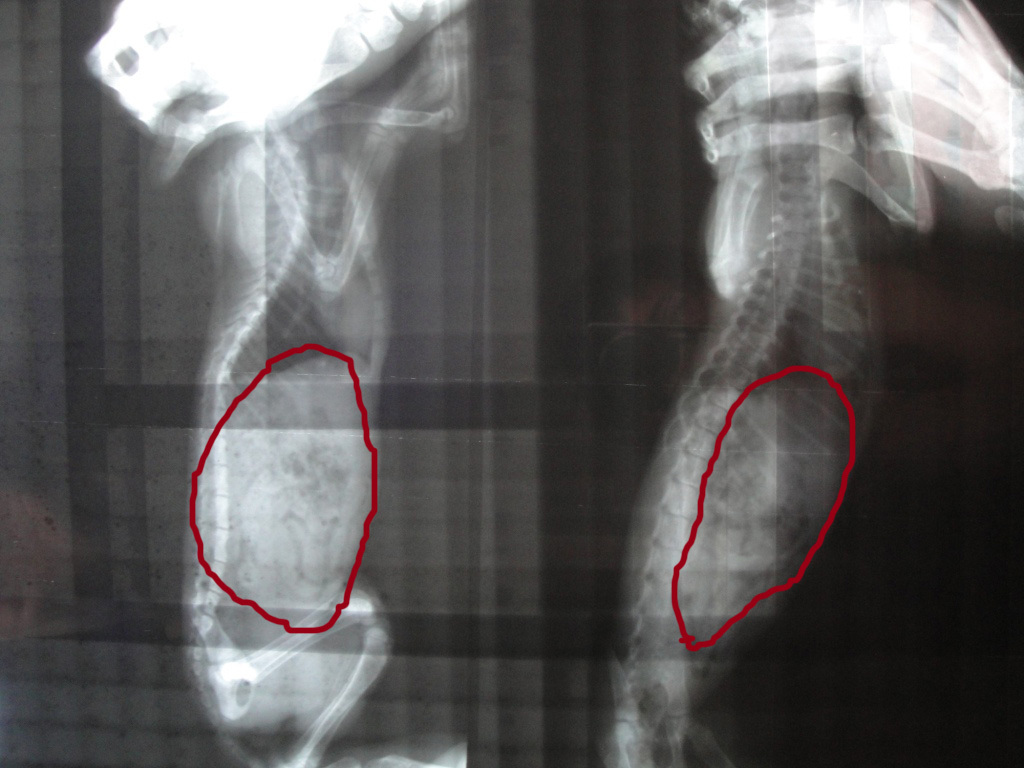

主題: 颱風天僅存的橘子貓 申請者姓名: 李承展 花色: 申請日期: 2012-06-26 22:27:11 申請者部落格: 申請者臉書網址: https://www.facebook.com/profile.php?id=100000695703990 所在縣市/合作醫院: 台北市/其他院所醫助專案(醫院請先MAIL溝通) 治療費用: 7800元 需求人數: 9人 已結案 (2012-12-01 20:33:00) 報名人員: 王駝、Vincent(已付款)、陳黑貓(已付款)、豬小妹(已付款)、Ariel Chang(已付款)、Shirley(已付款)、Vanna Tai(已付款)、SummerSha(已付款)、Amigo Yang(已付款)、林妮娜(已付款)、 候補人員: 黃偉倫、小舟、 動物病情說明: 在外頭與媽媽走丟 颱風天下大雨躲在車棚角落

由於是分租套房 車棚有許多雜物

其他兄弟姊妹都在大馬路上遭撞死

媽媽也就沒回來過 可能因肚子餓吃週遭的垃圾

初步診斷是塑膠類物品

因事態緊急只好馬上動刀 目前以撐過開刀

小貓血管過小 只能打皮下給予水分

目前仍在醫院治療中動物近況說明: 已帶回 目前少量多餐 避免傷口裂開

還是很乖黏人 知道自己的名子

復原狀況穩定